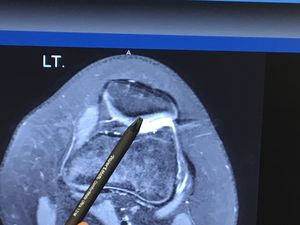

deterioration of cartilage (Pediatric)

25% loss of cartilage in a 14 year olds knee.

Orthopedic

Pediatric

Arthritis